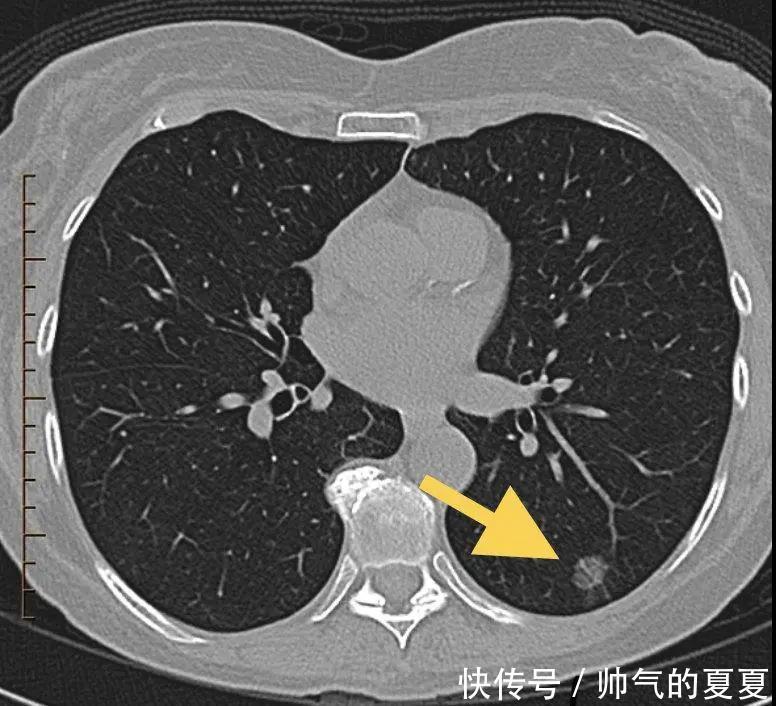

图2 ?纯磨玻璃结节第二种结节,实性结节(Solid Pulmonary Nodule, SPN)从CT图像看,结节的密度高,完全不透明了,已经看不到黑黑的肺组织,这就是实性结节。

文章插图

图3 ?实性结节第三种,混杂型磨玻璃结节(mixed Gross glass nodule,mGGN)这种结节处在前两者的“中间”,在CT图像上表现为磨玻璃和实性结节的混合,磨玻璃阴影里还带有,实性成分。